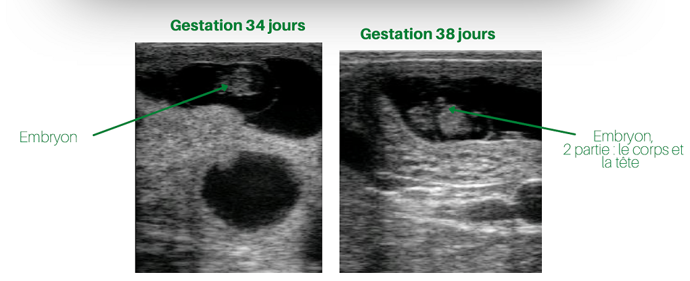

- À 30 jours, l’utérus est proche de la vessie. Il est alors possible de chercher la présence de liquide dans les cornes utérines. Il est également possible d’identifier l’embryon et de déceler un clignotement provenant des battements cardiaques.

- À partir de 40 jours, l’augmentation de liquide intra-utérin est déjà plus évidente et il devient possible d’observer des organes supplémentaires, comme l’œil. La fente des sabots est quant à elle observable autour de 45 jours, de même que la présence de mouvements fœtaux. Il est possible d’observer la présence des côtes aux environs des 53 jours.